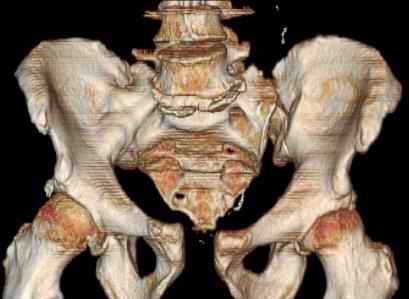

Hello gentlemen- Case is 52 YO male, fell out of treestand while deerhunting. He is 6 ft, approx. 260-275 lbs. Was hemodynamic unstable at local ER, sent to our Trauma center where circumferential pelvic binder placed and pt. stabilized with fluid, blood, and rewarming. Angiography not performed. An extraperitoneal bladder disruption was found, uro elected to treat non-operatively. Initial xray (not shown) demonstrated 5-7 cm wide at symphysis and SI joint. The first image attached is of CT once binder is in place. On post trauma day 5 the pt was taken to OR for ORIF of his iliac wing fracture and SI dislocation. The swelling/3rd spacing of fluid in the area of symphysis was profound, but quite acceptable posteriorly. Patient was prone for procedure, as I thought too difficult to fix the wing in lateral position. Of course the repair of wing was easy, but reduction of SI very demanding. The Floro images document the residual lack of reduction. That was the closest I could get it using 6mm joystick in wing, and clamp on sacrum and clamp through notch. The fixation was (initially) rigid. Anterior ex fix with supra-acetabular pins was placed due to condition of soft tissues, massive "beer-belly" overhanging the crest. Post trauma day ten patient's xray shows failure of posterior construct. Plan was to perform revision orif once soft tissues resolve considerably for full anrterior fixation and posterior fixation. However, while Im away for holiday (on Post trauma day 15), pt is developing septic clinical appearance, and trauma suspects pelvic abcess near symphysis and performs I and D - finds nothing but no primary closure performed. Posterior tissues/incision continue to look healthy. Now is post trauma day 17, pt is still tubed/on dopamine/and wbc still elevated, anterior incision still packed open. Clearly must get to bottom of possible sepsis, but then what? Thanks for you time - sorry for such lengthy clinical description. Thomas Schaller Kalamazoo, Michigan

Request for more images.. Axial and coronal recon (pt in binder.)